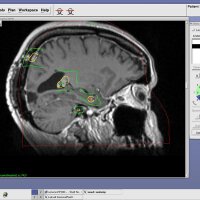

Being diagnosed with cancer is difficult…learning that it has spread to the brain can be devastating.